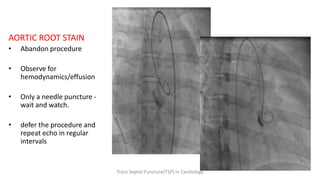

AORTIC ROOT STAIN

• Abandon procedure

• Observe for

hemodynamics/effusion

• Only a needle puncture -

wait and watch.

• defer the procedure and

repeat echo in regular

intervals